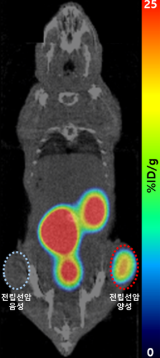

사진4. 전립선암 음성 대조군과 양성 실험군이 심어진 쥐에 주입한 갈륨-68 PSMA-11 체내영상

※ PSMA, prostate specific membrane antigen (전립선특이막항원)

설명 : 전립선암 음성 대조군과 달리, 우측 허벅지의 양성 실험군의 종양 부위에만 갈륨-68 방사성의약품이 선택적으로 집적되며 갈륨-68 발생기의 유효성을 성공적으로 검증

□ 또한 연구진은 이번에 개발된 소재로 용출한 갈륨-68을 이용해 분당서울대병원 핵의학과와 공동으로 전립선암 진단용 방사성의약품의 비임상 실험을 수행하여, 종양 영상 확보를 통해 갈륨-68 발생기 핵심 소재의 유효성을 성공적으로 검증했다. 해당 기술은 국내·외 특허등록을 완료했으며, 향후 방사성의약품을 개발하는 국내 기업에 기술이전이 추진될 예정이다.